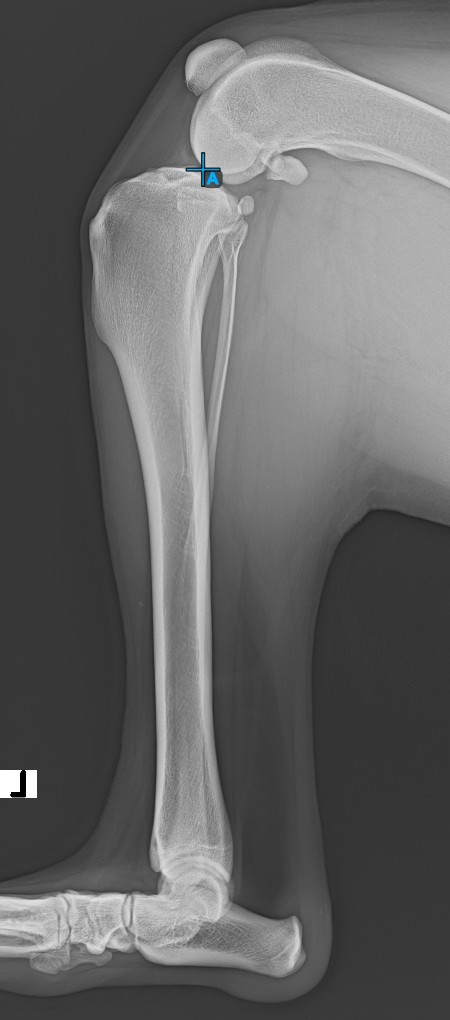

../../_images/image44.jpg

The TPA Angle (Tibial Plateau Angle) is one of the most important orthopedic measurements in veterinary medicine, measuring the slope of the tibial plateau relative to the long axis of the tibia. Select the TPA Angle measurement from the Advanced Measurement menu and assign the left mouse button to it.

The TPA Angle measurement is a crucial part of planning corrective surgeries, like TPLO (Tibial Plateau Leveling Osteotomy). Extend the TPA Angle measurement with TPLO in the simple viewer settings.

Start the measurement by marking the Eminentia Intercondylaris, which is located on the joint connecting the femur and the tibia.

The image below depicts the usual placement of the Eminentia Intercondylaris point.